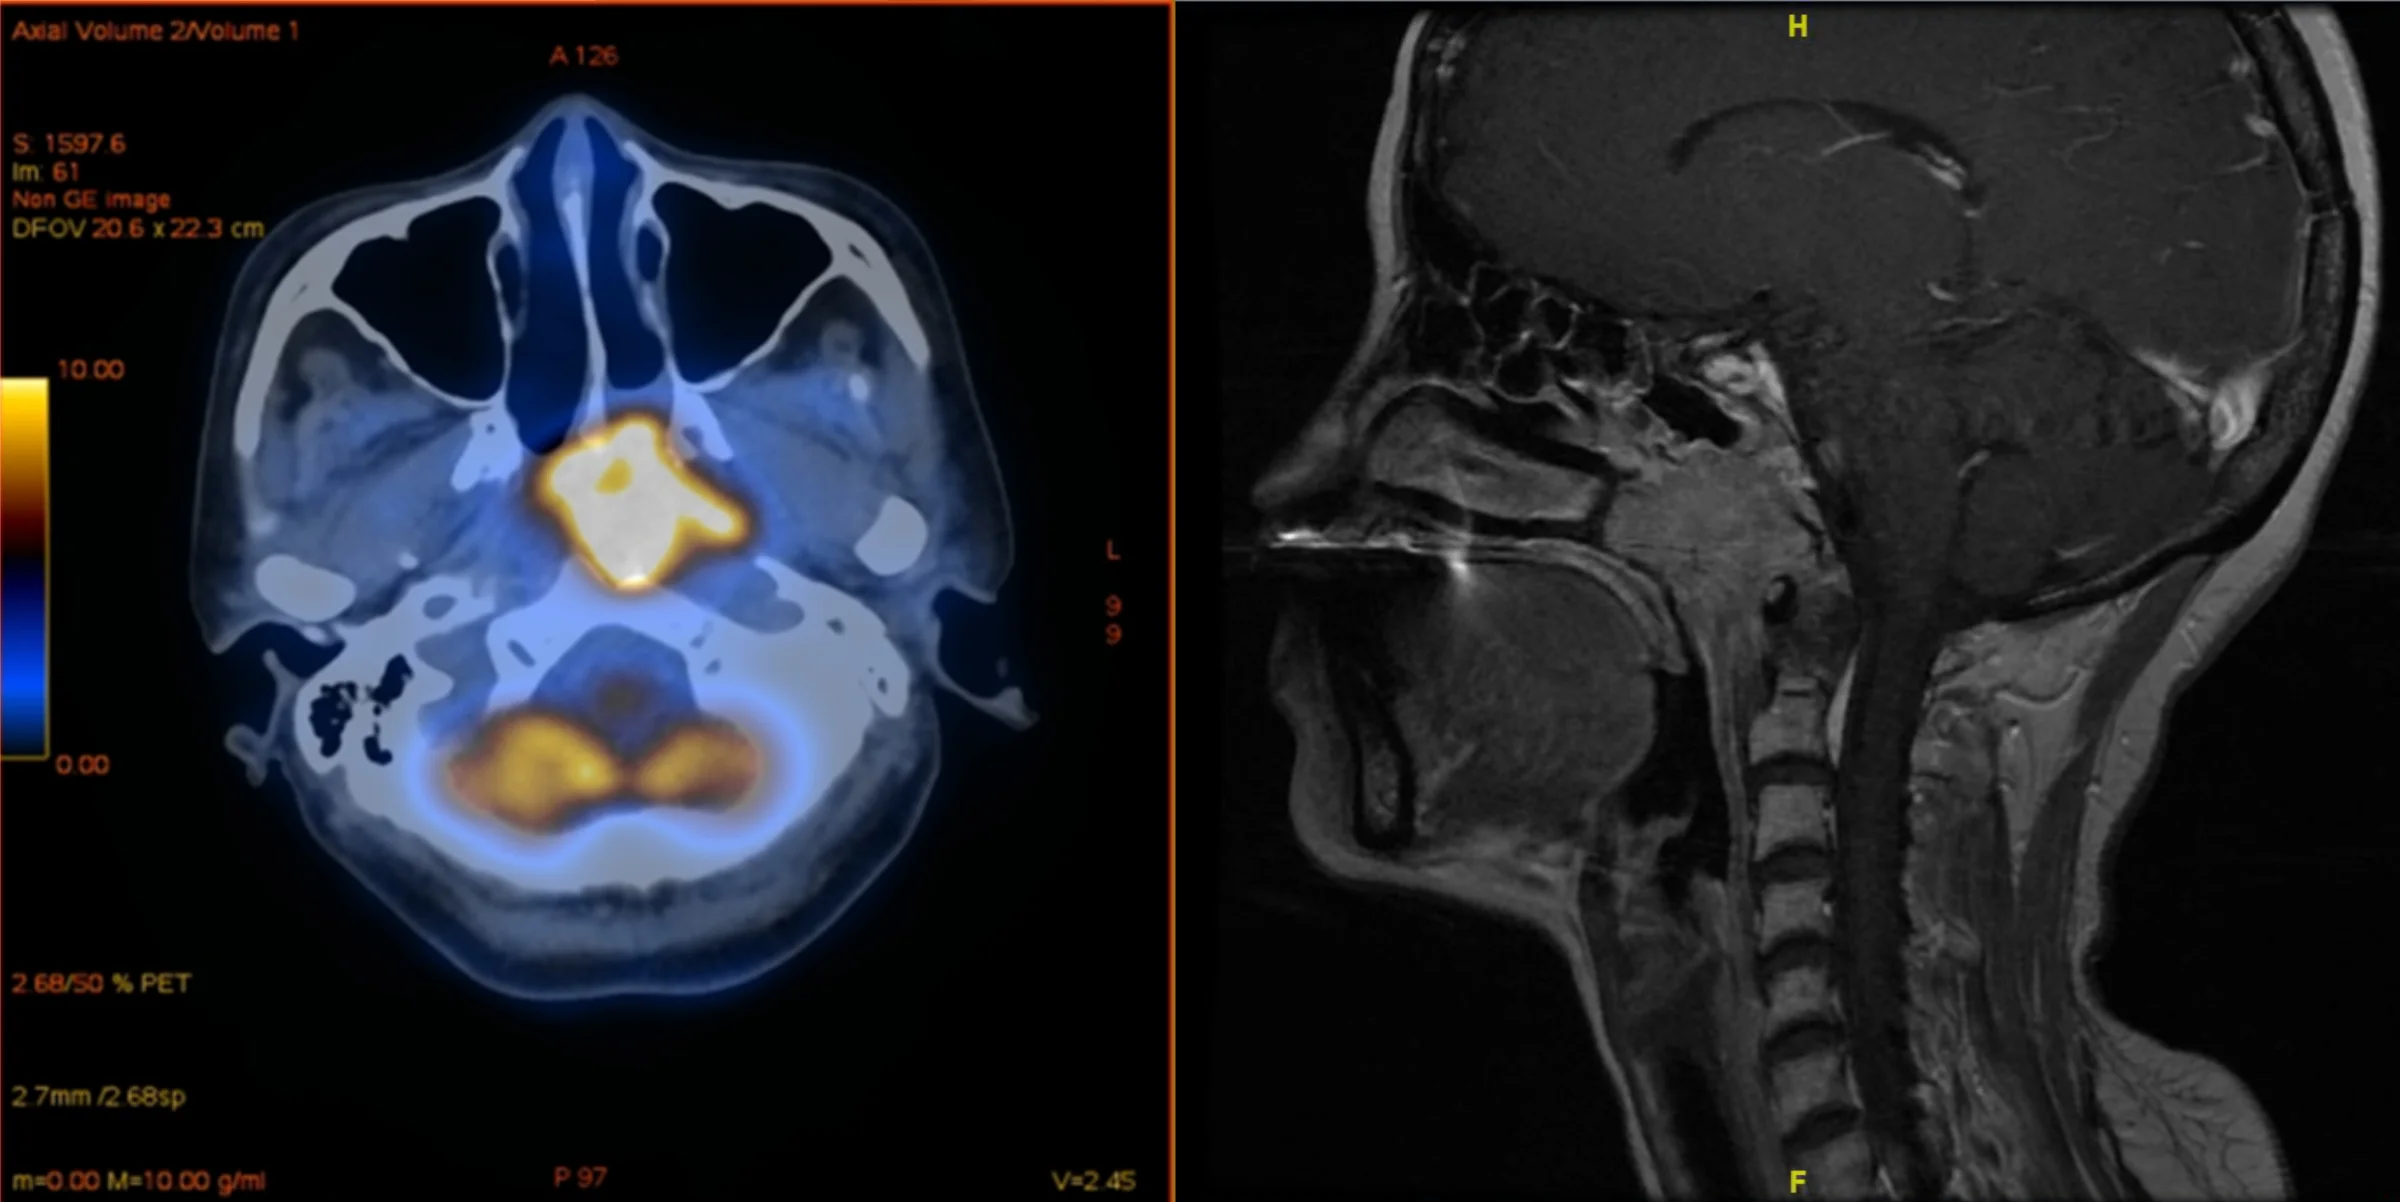

Nasenrachentumore (gelb markiert) Zurück